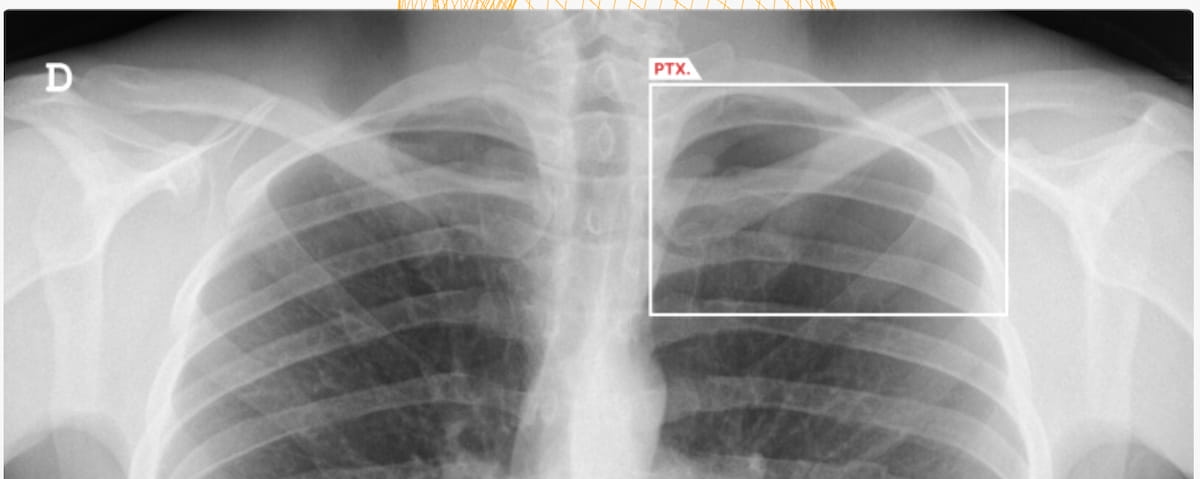

The Food and Drug Administration (FDA) has granted two 510(k) clearances for the artificial intelligence (AI)-enable software AZchest for chest X-rays (CXRs). In addition to lung nodule detection, the AZchest software has been cleared for triage of cases involving pneumothorax or pleural effusion.

Recent research revealed 93.79 percent sensitivity and a 98.57 percent area under the receiver operating characteristic curve (AUC) for detection of pneumothorax with